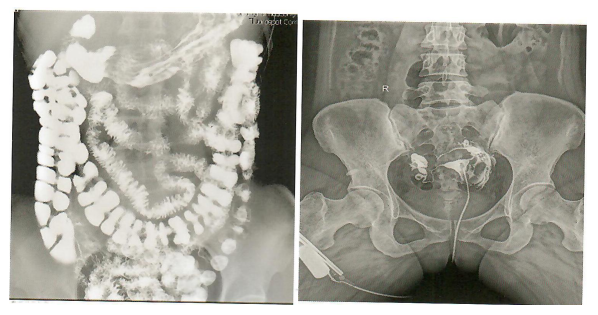

北斗系列数字透视摄影系统,毫秒抓拍,满足多种临床诊断需求,低剂量高转换率,瞬间曝光绿色安全,采用先进脉冲透视技术,结合高标准的硬件配置,使超低剂量与高清图像完美融合,全新的自动剂量控制系统,以更小的辐射剂量获取更清晰的图像信息,减少射线对医患的辐射。

精准诊断,卓越超群的影像质量,毫秒抓拍,满足多种临床诊断需求。

食道造影 胃肠造影

全消化道造影 其它照影